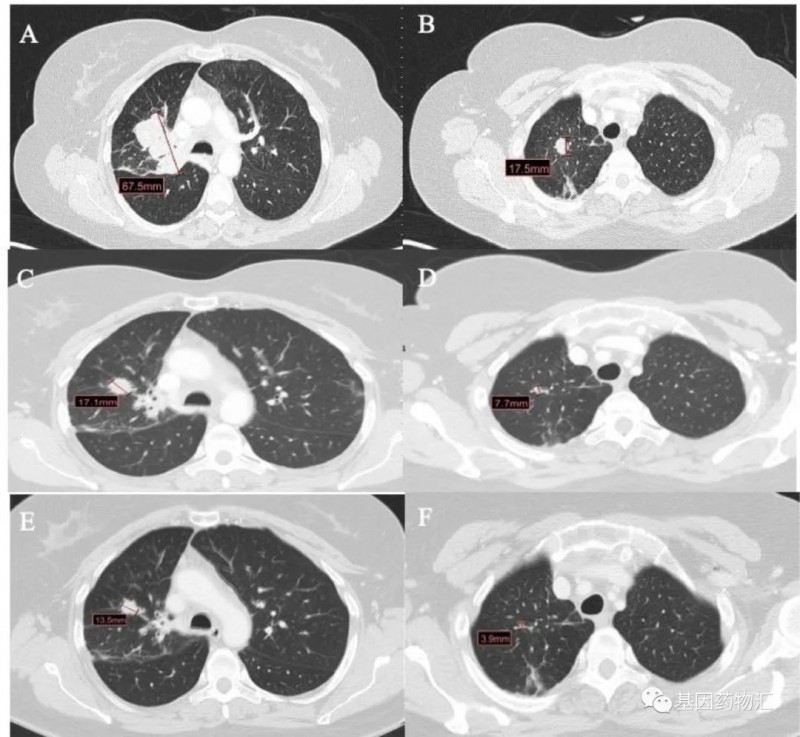

相似的案例也是有的。一位49岁的女性患者,罹患Ⅳ期肺腺癌,且测试存在EGFR ex20ins阳性,为EGFR P772_H773insPNP和TP53共突变。

患者从2018年7月开始接受卡铂+培美曲塞治疗,4个周期后继续使用培美曲塞维持治疗1年。至2019年7月患者复查CT时发现肺部和淋巴结进展,于是接受了Amivantamab(JNJ-6372,JNJ-61186372)的治疗,再次达到临床缓解,持续了9个月。

至2020年5月,患者出现了严重的背痛症状,CT检查显示骨骼与淋巴结进展。患者接受了姑息性放疗,以及多西他赛+尼达尼布(Nintedanib)方案治疗,但提示了疾病进展。

此后患者接受了Mobocertinib(TAK-788)的临床试验,达到了临床缓解,症状显著改善。至结果发布时,患者的疗效已经持续了超过8个月。